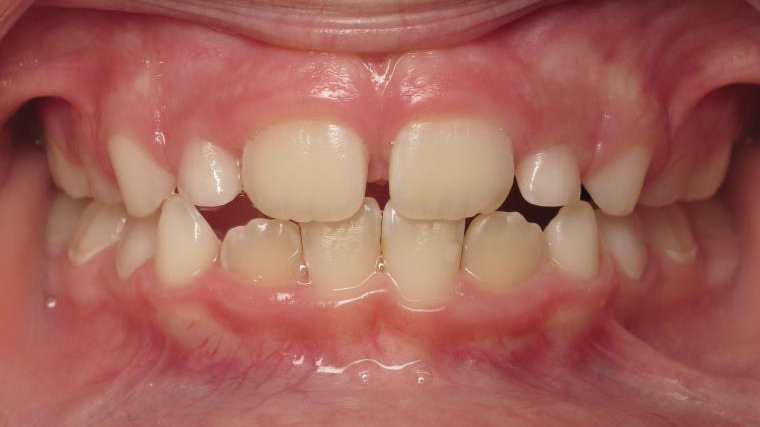

sectionnel multibagues

surveillance évolution de la dentition pendant 4 ans

bilan début fin de traitement